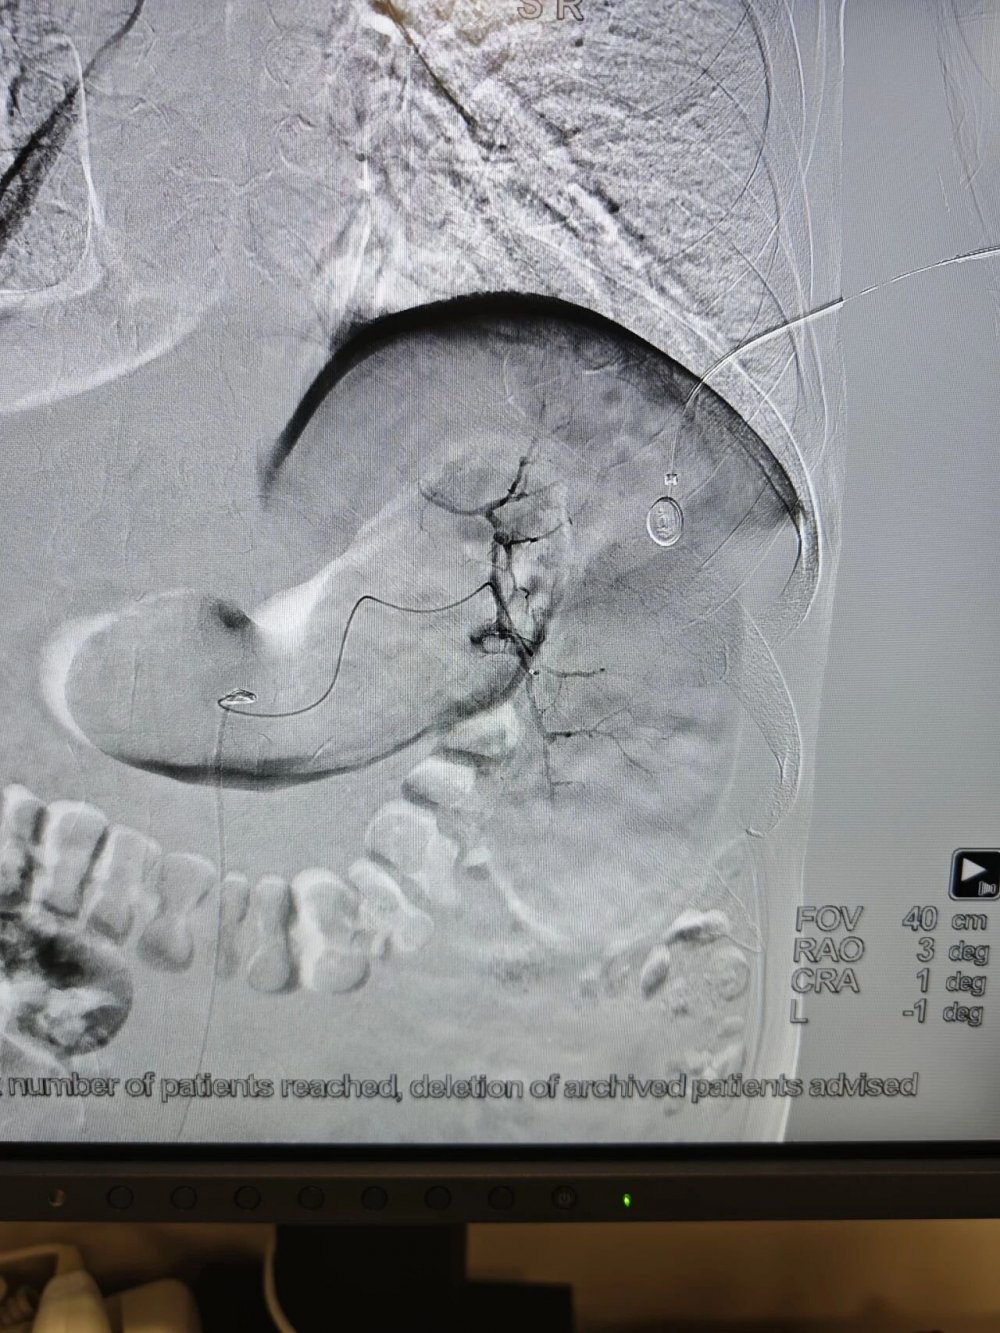

手术全程在数字减影血管造影(DSA)高清影像实时监控下开展,全程可视化操作,精准、安全、可控。

术中,介入医学科负责人卜高峰通过微细导管沿血管通路精准送达脾动脉主干,精准定位异常增生、过度亢进的病变脾组织血管分支,注入专用栓塞颗粒,选择性阻断脾脏病变区域血供,让亢进的脾组织逐步缺血萎缩,从根源解决脾功能亢进问题。

手术中,导管精准抵达脾动脉位置,清晰显示脾脏血管供血形态,为后续栓塞操作提供精准定位

栓塞过程中,通过导管向病变脾组织血管注入栓塞颗粒,精准阻断异常供血,最大程度保留正常脾组织。